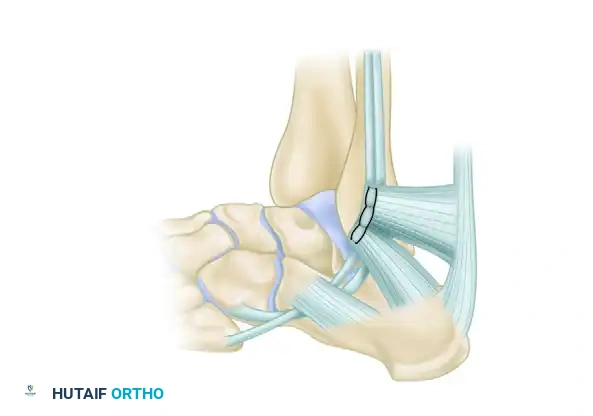

Lateral view of the completed repair. The repaired peroneal retinaculum is securely attached under the deep anterior surface of the groove, restoring the anatomical fibro-osseous sheath.